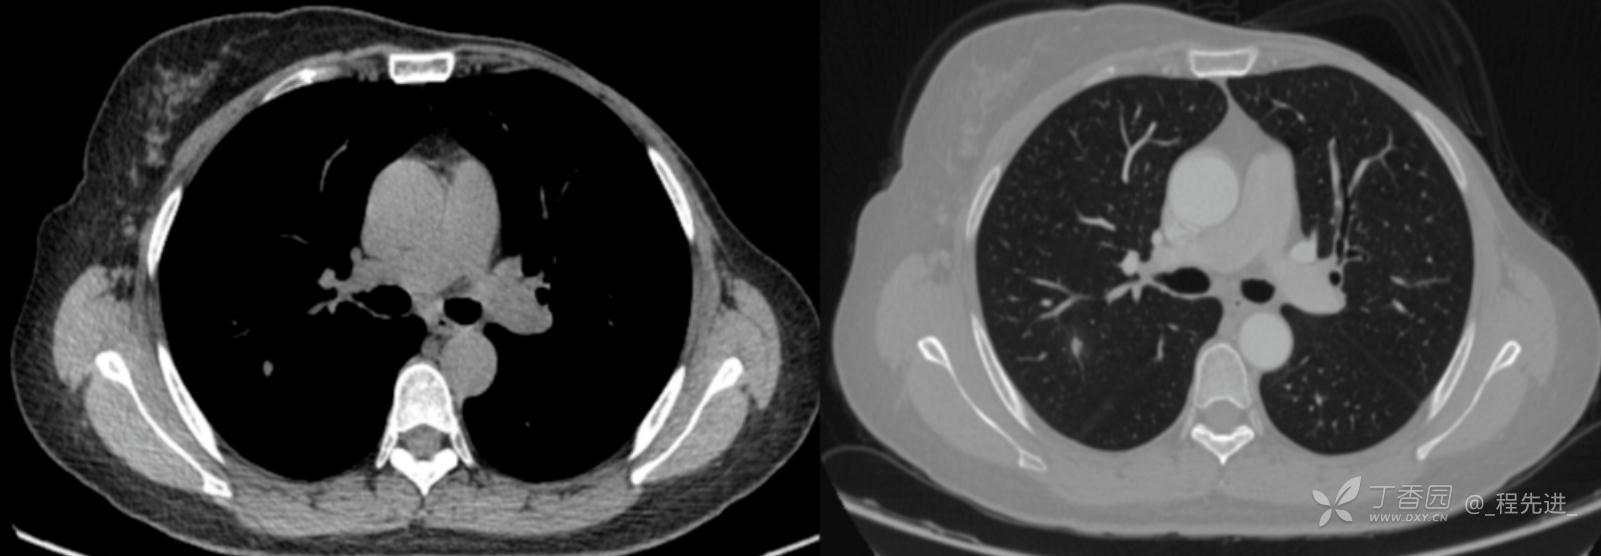

患者性别:女

患者年龄:52岁

简要病史:体检发现右肺上叶结节

既往史:左乳腺癌术后,化疗后

机化性肺炎 (42)

肺结核 (246)